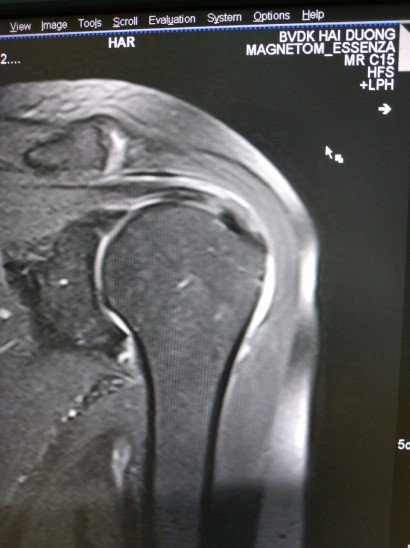

Hình ảnh điển hình tổn thương GCX

Hình 4. Hình ảnh tổn thương gân cơ trên gai